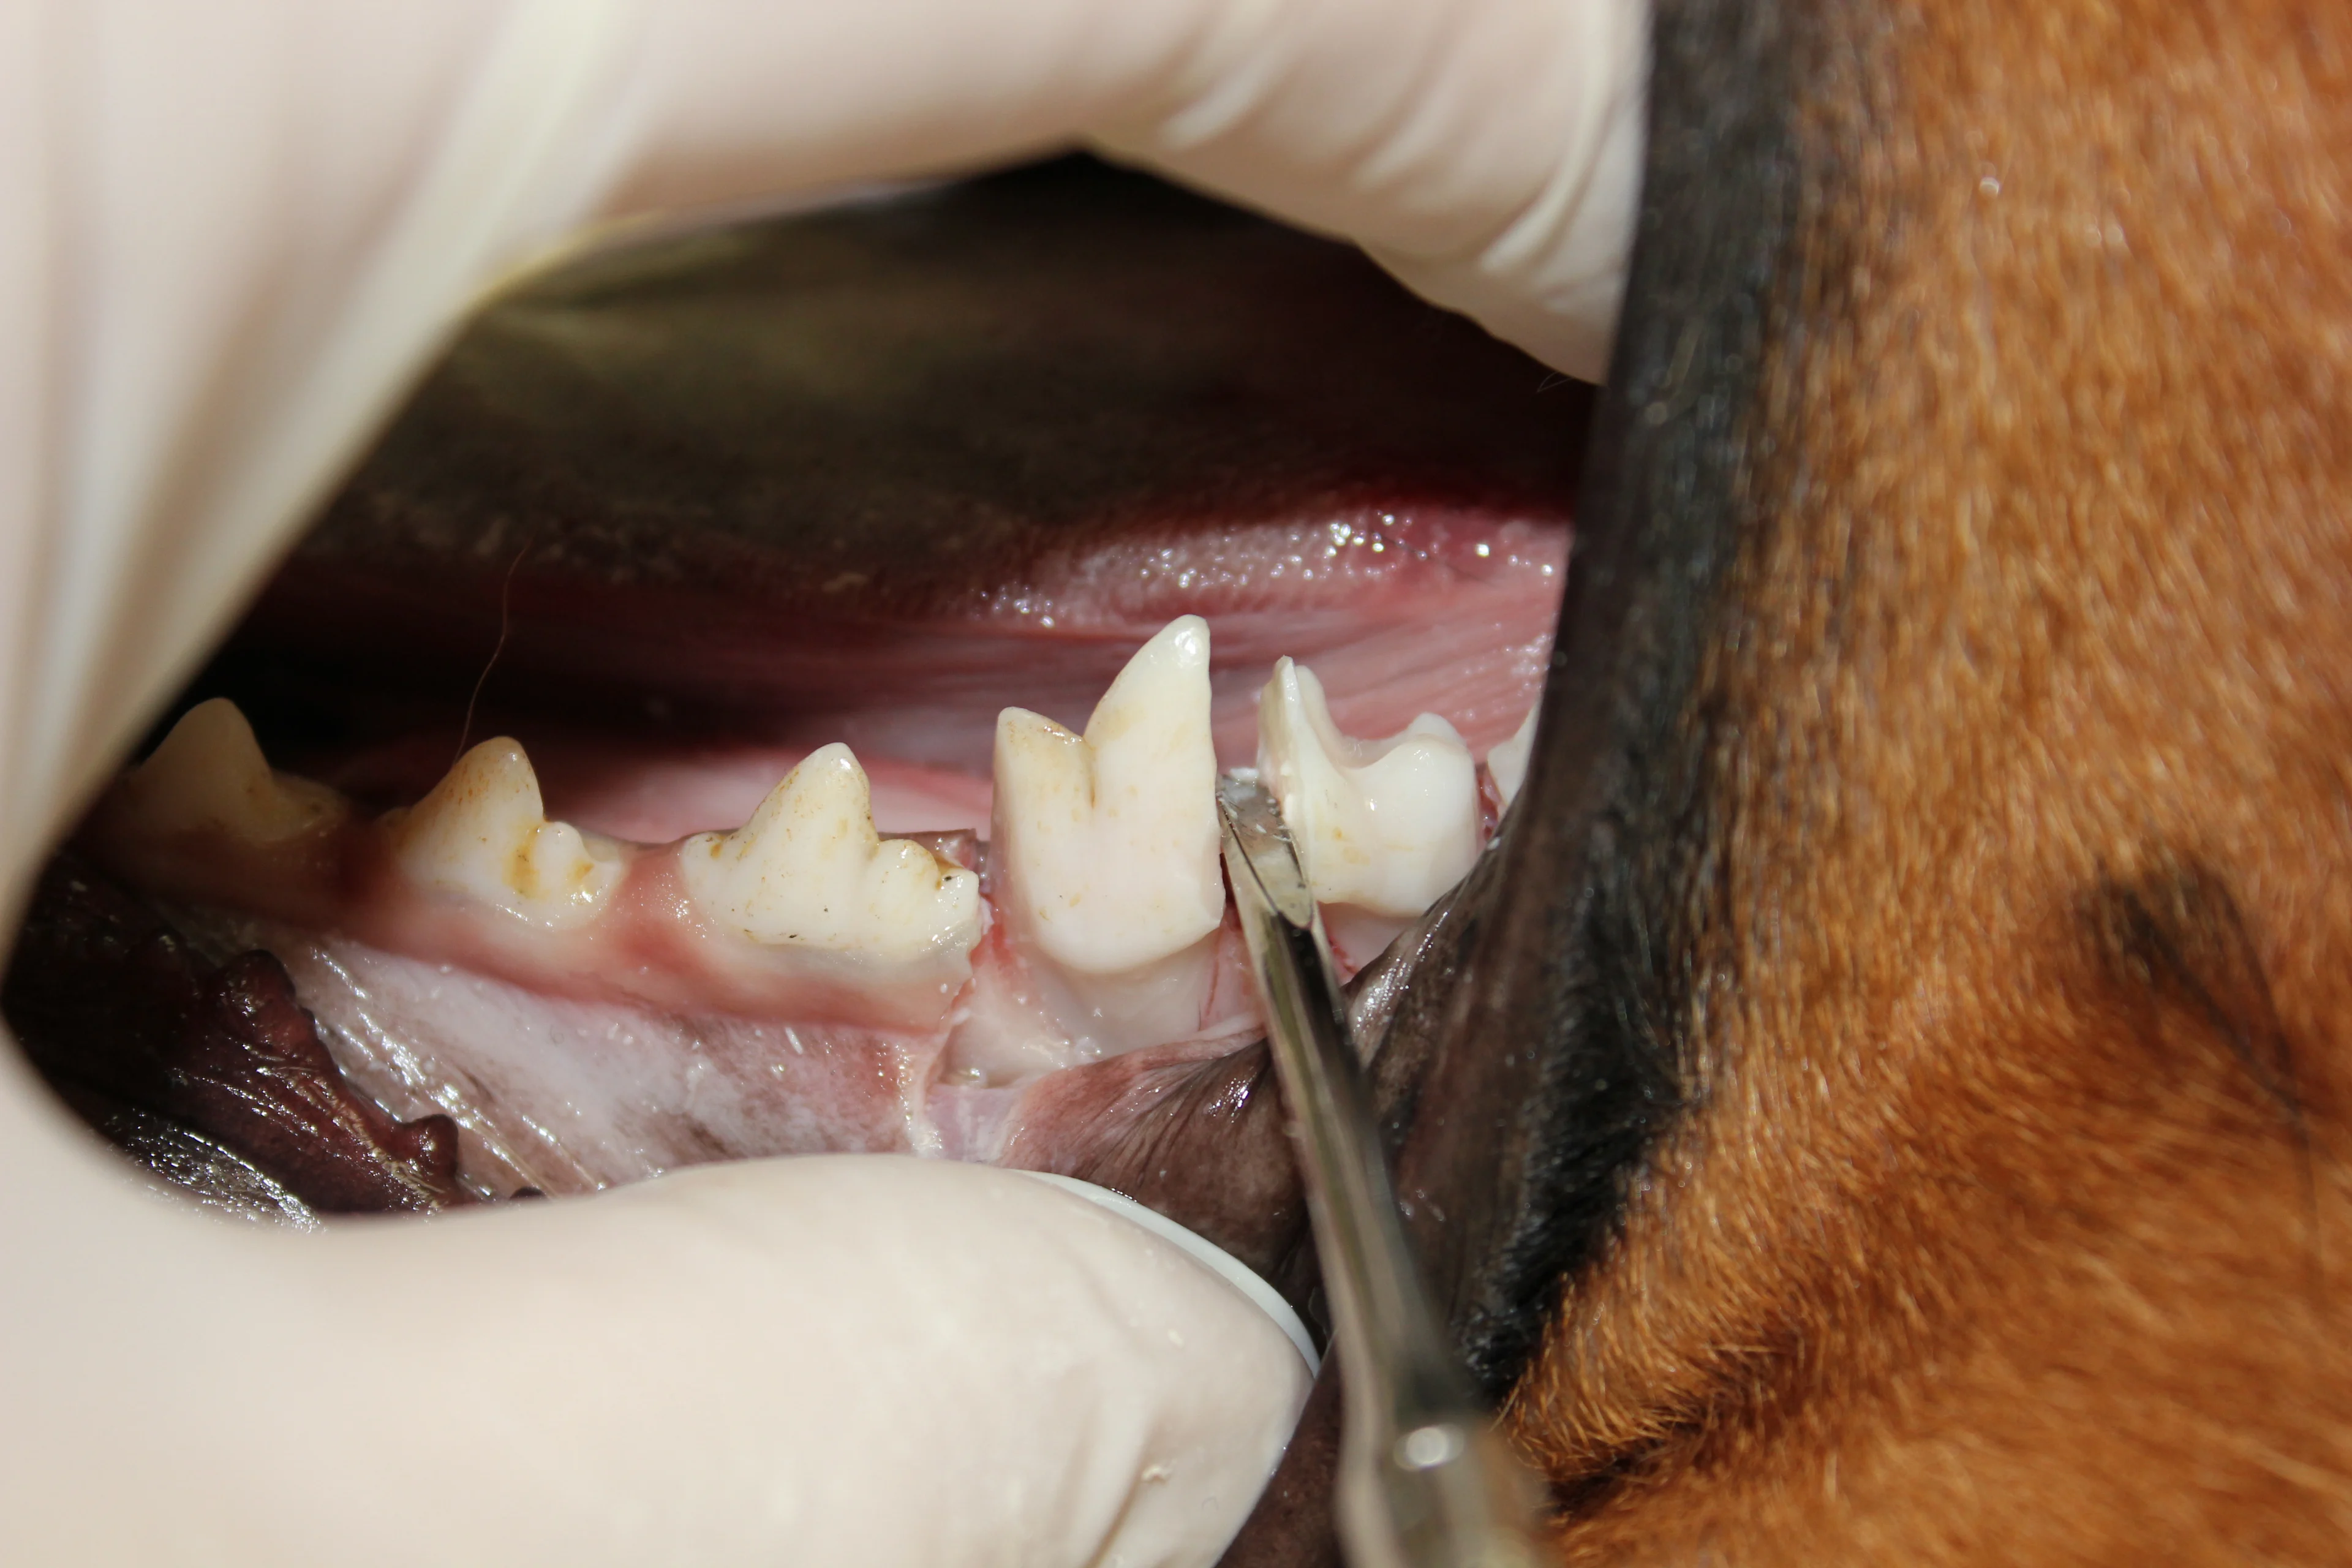

Step 7

Remove tooth structure on the mesial and distal surfaces (odontoplasty) to allow space for the elevator to slide into the periodontal ligament space. Position the #701L bur parallel to the tooth axis. The mesial and distal portions of the crown may be removed to facilitate extraction by gaining access to the periodontal ligament. Take care not to damage the fourth premolar and second molar teeth.

Find the periodontal ligament space and elevate the mesial root (larger of the 2 roots) followed by the distal root. (A) Place a finger stop on the tip of the presharpened elevator/luxator and gently slide it into the periodontal ligament space. Rotate the elevator/ luxator until resistance is met, hold for 15 seconds, then repeat by rotating in the opposite direction. Move the elevator/luxator around the ligament space and repeat until completely around the tooth segment. (B) When the tooth segment becomes mobile, use the extraction forceps to rotate the segment until resistance is met, hold for 15 seconds, then repeat in the opposite direction. Position the jaws of the extraction forceps parallel to the axis of the tooth root. Once the mesial root has been extracted, repeat the procedure for the distal root.